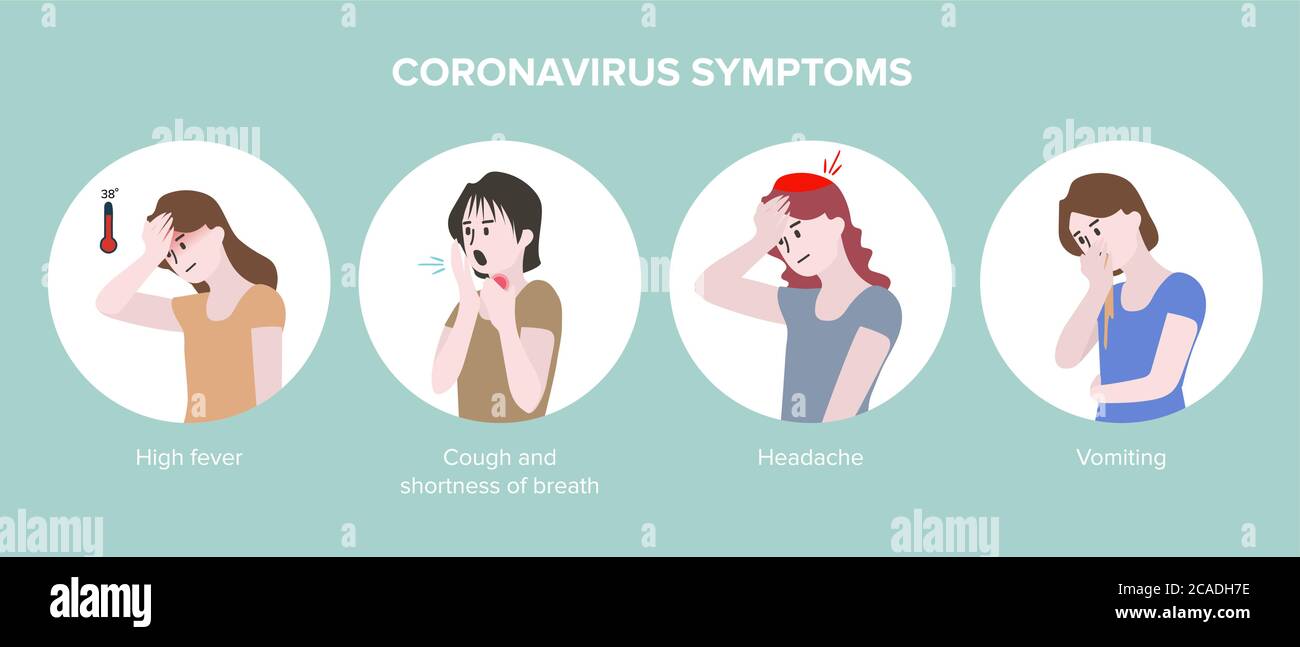

RF2CADFNB–Segno infografica con Cartoon ha tosse, febbre, Gola irritata e freddo in Coronavirus o Covid-19 focolaio.